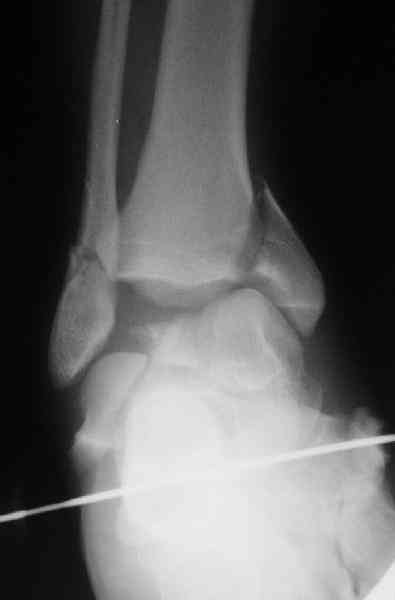

Interesting case

The ankle joint looks ruined. I wonder howcome is it as ruined after 2 days. I would open the joint( Some people would artroscope it) and judge the osteosynthes vs ankle fusion according to the ankle joint condition. The subtalar does not look injured, but if you feel there is a clinical

problem- CT it. Above all- when I see such an X-Ray I call the resident who ordered it and tell him that I would expect him first thing to reduce it on arrival since the soft tissue suffer and I hope that currently the p-nt is reduced to some extent at least.

Sorry- I revised it and the talus is fractured- take him to the theater at once and reduse it with Int Fix

The soft tissue will be a problem- Ex Fix will be better thn plaster

а основании двух видов ренгенограмм невозможно радикально решить о необходимости открытой репозиции или первичного артродеза.

Для оценки состояния нужны дополнительные исследования, например Canale или Broden ренгенограммы и Компьютерная томография.

При переломах тарана всегда имеется риск AVN, а классификация Hawkins поможет разобраться с предполагаемыми осложнениями.

Если в первом типе, когда перелом шейки без смещения, тогда AVN менее 10%, при втором типе когда имеется смещение и вывих тарана в субталарном сочленении меньше 40%, а при типе III когда смещение в голеностопном и субталарном суставах - около 90% и в типе IV, когда происходит полный вывих, риск AVN достигает 100%.